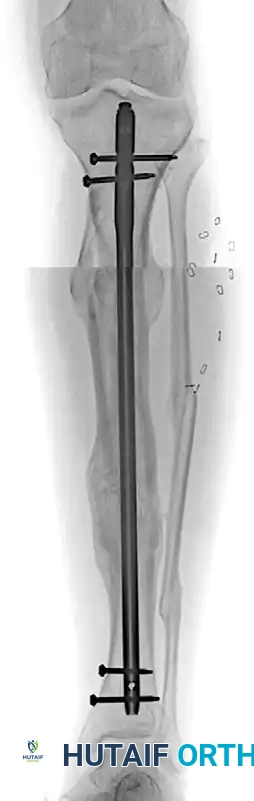

FIGURE 58-18: A, Deformity correction in the coronal plane utilizing the clamshell osteotomy technique. B, Sagittal plane correction demonstrating the restoration of the anatomical axis prior to intramedullary nailing.

FIGURE 58-19 (A): Anteroposterior radiograph 1 year after surgery, demonstrating a healed clamshell osteotomy with excellent restoration of tibial length, coronal alignment, and joint orientation.